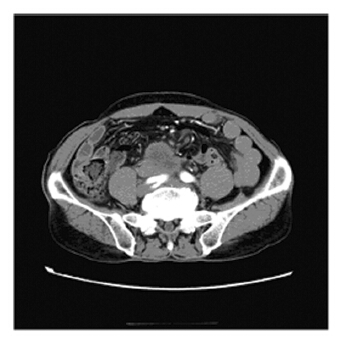

患者,男,67岁,以主诉“下腹疼痛3月余” 于2013年9月1日入住泸州医学院附属医院,3月前 无明显诱因出现下腹疼痛,无尿频、尿急、尿痛 等排尿困难。曾于1年前出现1次肉眼血尿伴血凝 块。查体:左右肾区无隆起,肋腰点压痛(-), 双肾区叩诊(-),双肾动脉血管杂音(-)。 B型超声提示右输尿管近跨髂血管腔内减弱回声 团,右肾盂积水。CT提示右侧输尿管中段管壁增 厚,管腔狭窄、闭塞,腹主动脉下端分叉处见一 分叶状软组织肿块影,密度不均,考虑输尿管可 能性大。右输尿管上段及右肾盂扩张积水,见图 1。全麻下行右肾+右输尿管中上段切除术。术中 见右肾重度积水,皮质菲薄,右侧输尿管重度畸 形,中段以上输尿管肿胀、质硬,与周围粘连明 显,其上输尿管扩张、积水。术前诊断:(1)右 肾重度积水;(2)右肾无功能;(3)输尿管肿 瘤?

| Enhanced CT showed that the middle of ureter was thickened with mass lesion in the lower abdominal aorta 图 1 肾盂输尿管浸润性尿路上皮癌患者的增强CT Figure 1 Enhanced CT of patient with infiltrating urothelial carcinoma of renal pelvis and ureter |

肾盂、输尿管癌早期诊断困难,易漏诊误 诊。本例增强CT提示肾盂扩张积水,输尿管管壁 增厚狭窄,腹主动脉下端分叉处可见软组织肿块影,临床诊断右肾重度积水,右肾无功能,可疑 输尿管肿瘤,而病理巨检时可见肾盂及输尿管内 肿块组织,病检结果提示肾盂及输尿管浸润性尿 路上皮癌,由此可见病理检查在临床诊断中起着 重要作用。肾盂、输尿管癌易漏诊误诊另一原因 是临床症状不典型,尤其是原发性输尿管尿路上 皮癌,镜下血尿可能是肾盂、输尿管肿瘤浸润的 首发症状,Demirci等[5]对11例肾盂和输尿管浸润 性尿路上皮癌研究发现,8例患者首发无痛性肉眼 血尿,3例首发腹部疼痛,本例曾出现过1次肉眼 血尿,主要表现是近月来下腹疼痛,考虑可能是 肿瘤出血凝集成血块,通过输尿管部发生慢性阻 塞,加上肾盂积水扩张,导致疼痛。